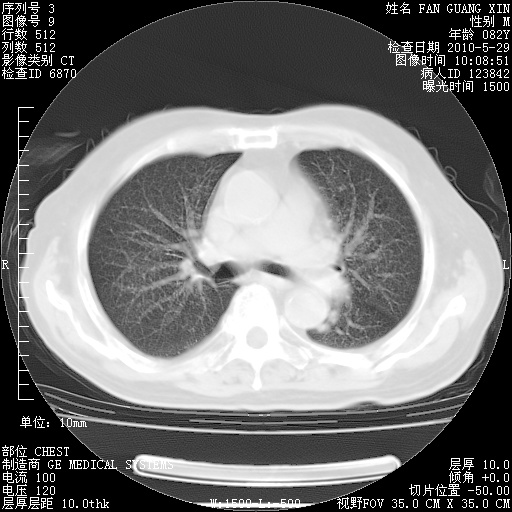

再治疗10天后的肺部CT

从白细胞总数和中性比例看好像合并感染。肺部纹理好像比上次多,支气管炎?其他感染?

阅读此次胸部CT,肺间质渗出性改变较入院时有吸收。目前从体温、白细胞、中性分叶明显增高,肯定存在细菌感染(发生医院感染哦,若无消化道及泌尿系统等感染的依据,肺部感染可能大)。若你院头孢哌酮舒巴坦钠耐药率较高,同意你的方案,若48小时体温仍高,可考虑使用碳青霉稀类抗菌药物,同时可予超声雾化、注意滴数时加大液体量。白蛋白33.30g/L较低哦,需加强营养等支持治疗。